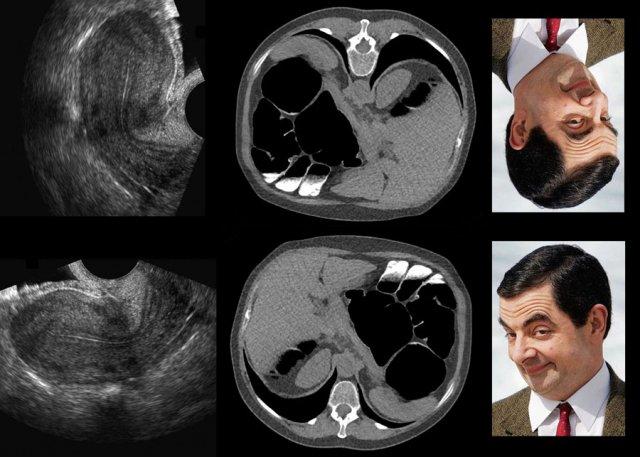

Tương tự, mặc dù thông tin hình ảnh của hai bức chân dung Mr. Bean là giống hệt nhau, nhân vật hài hước này dễ nhận ra hơn nhiều khi ảnh treo đúng chiều so với khi treo ngược.

Để hiểu đúng hình ảnh TVUS của DIE, đặc biệt là mối tương quan với hình ảnh MRI, điều quan trọng là phải nhận thức được sự khác biệt về định hướng được sử dụng trong hai phương thức hình ảnh này.

Trong ba hàng trên, “định hướng MRI” chiếm ưu thế, và do đó hình ảnh TVUS ở góc trên bên phải đã được: 1. lật ngang (ảnh gương) và 2. xoay ngược chiều kim đồng hồ khoảng 120 độ.

Mặc dù có thể lập luận rằng hình ảnh đã lật và xoay này tương ứng tốt hơn với MRI mặt phẳng đứng dọc, nhưng việc nhận dạng hình thái học được hỗ trợ tốt hơn khi sử dụng góc nhìn TVUS “kinh điển”, như được hiển thị trong hình ảnh phía dưới.